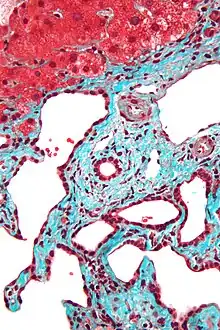

- Histopathology of a bile duct hamartoma, high magnification, H&E stain. It shows typical features of bile duct hamartoma:

- Micrograph of a bile duct hamartoma. Trichrome stain. Intermediate magnification

- Micrograph of a bile duct hamartoma. Trichrome stain, high magnification